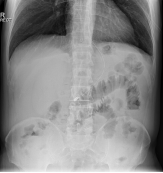

The patient presented again in the emergency after 7days from discharging from hospital, with complaints of abdominal distension and the inability to pass flatus and motion for 2days. This was associated with multiple episodes of vomiting. Clinical examination showed a distended abdomen with generalized mild tenderness and increased bowel sounds. X-ray showed multiple air-fluid levels. Routine laboratory investigations were within normal limits. The patient was initially managed conservatively with nil per oral, nasogastric tube suction, intravenous fluids intravenous antibiotics and other supportive management for 48h. However, in view of the persistence of intestinal obstruction, a decision to interfere surgically was made.

Figure 2 Plain erect xray- showing intestinal obstruction